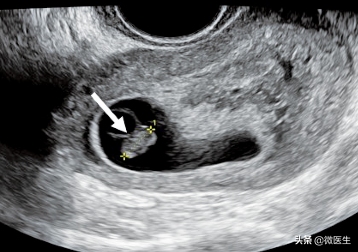

(6)胚胎停育经腔内超声检査胚胎长度≤5mm,7~10天后复查仍无心管搏动:或胚胎长度5mm,无心管搏动;或妊娠囊平均内径20mm,内未见卵黄囊、胎芽,可诊断胚胎停育。经腹部超声检査胚胎长度≤9m无心管搏动,7~10天后复查仍无心管搏动;或胚胎长度9m,未能观察胎心搏动;或妊娠囊平均内径25mm,未见卵黄囊、胎芽,可诊断胚胎停育。

孕9周,经腔内超声检查,胎芽长0.97cm,未见胎心搏动,胚胎停止发育